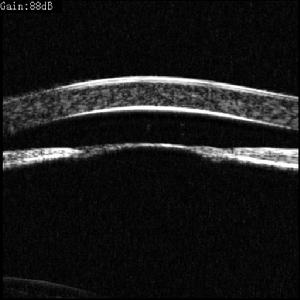

4.前房積血 是房角後退的徵兆之一。對前房積血的病人,一旦出血吸收,立即作房角鏡檢查。伴有前房積血的病例,作超聲生物顯微鏡(UMB)檢查可發現房角後退病變。

其它輔助檢查:眼部外傷多數情況下需利用CTMRI排除顱內病變情況。B超UBM可以明確球內以及眼前節的重要病變情況,尤其在出現積血而影響觀察時。